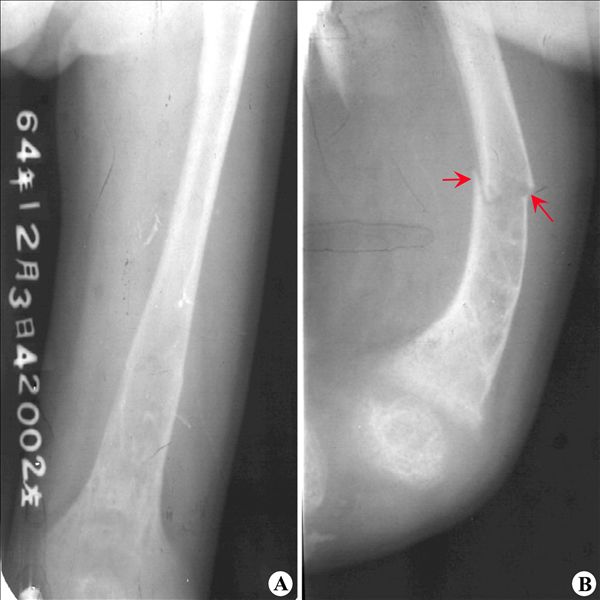

【影像表现】:X线正、侧位片(A、B)示股骨骨质疏松,矿化不足,变形;股骨远端干骺端膨大,骨质模糊,股骨中段可见病理骨折(B,↑)。

【影像诊断】:Fanconi综合征。